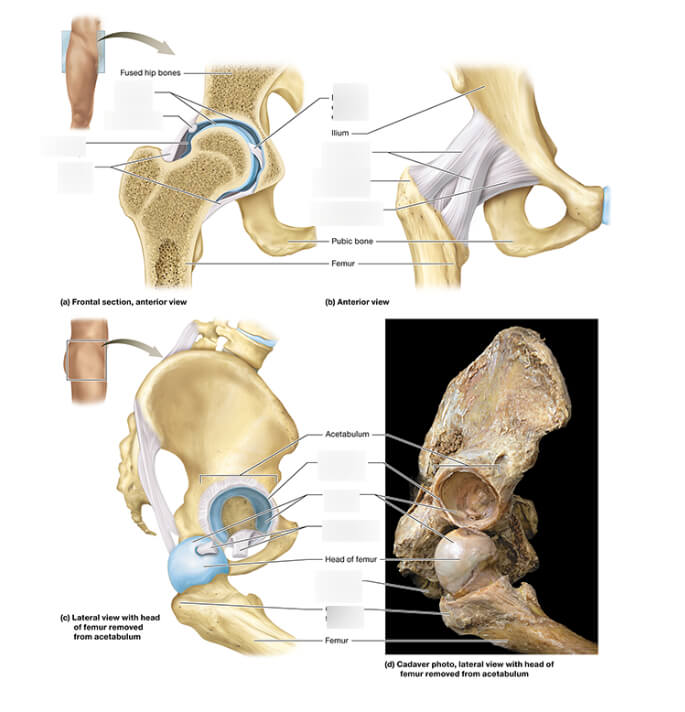

Het heupgewricht is een biomechanisch eenvoudiger gewricht dan het kniegewricht. Het betreft een bol in kom gewricht met de bol zijnde het bovenste uiteinde van het bovenbeen (femur) en de kom (acetabulum) deel uitmakend van het bekken.

Zoals bij elk gewricht wordt het uiteinde van het bot bekleed met kraakbeen (cartilago)

Het heupgewricht ligt diep in het lichaam en wordt afgelijnd door een fibrocartilagineuze boord (labrum) en een zeer stevig kapsel. Rond het heupgewricht liggen ook zeer grote stevige spiergroepen ter stabilisatie van het bekken en de heup.